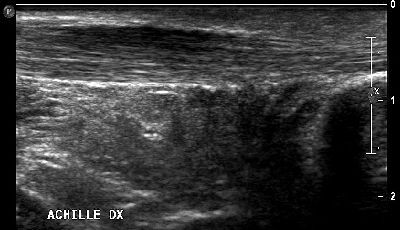

Tendinopatia achillea Lesione tendine d'Achille 02